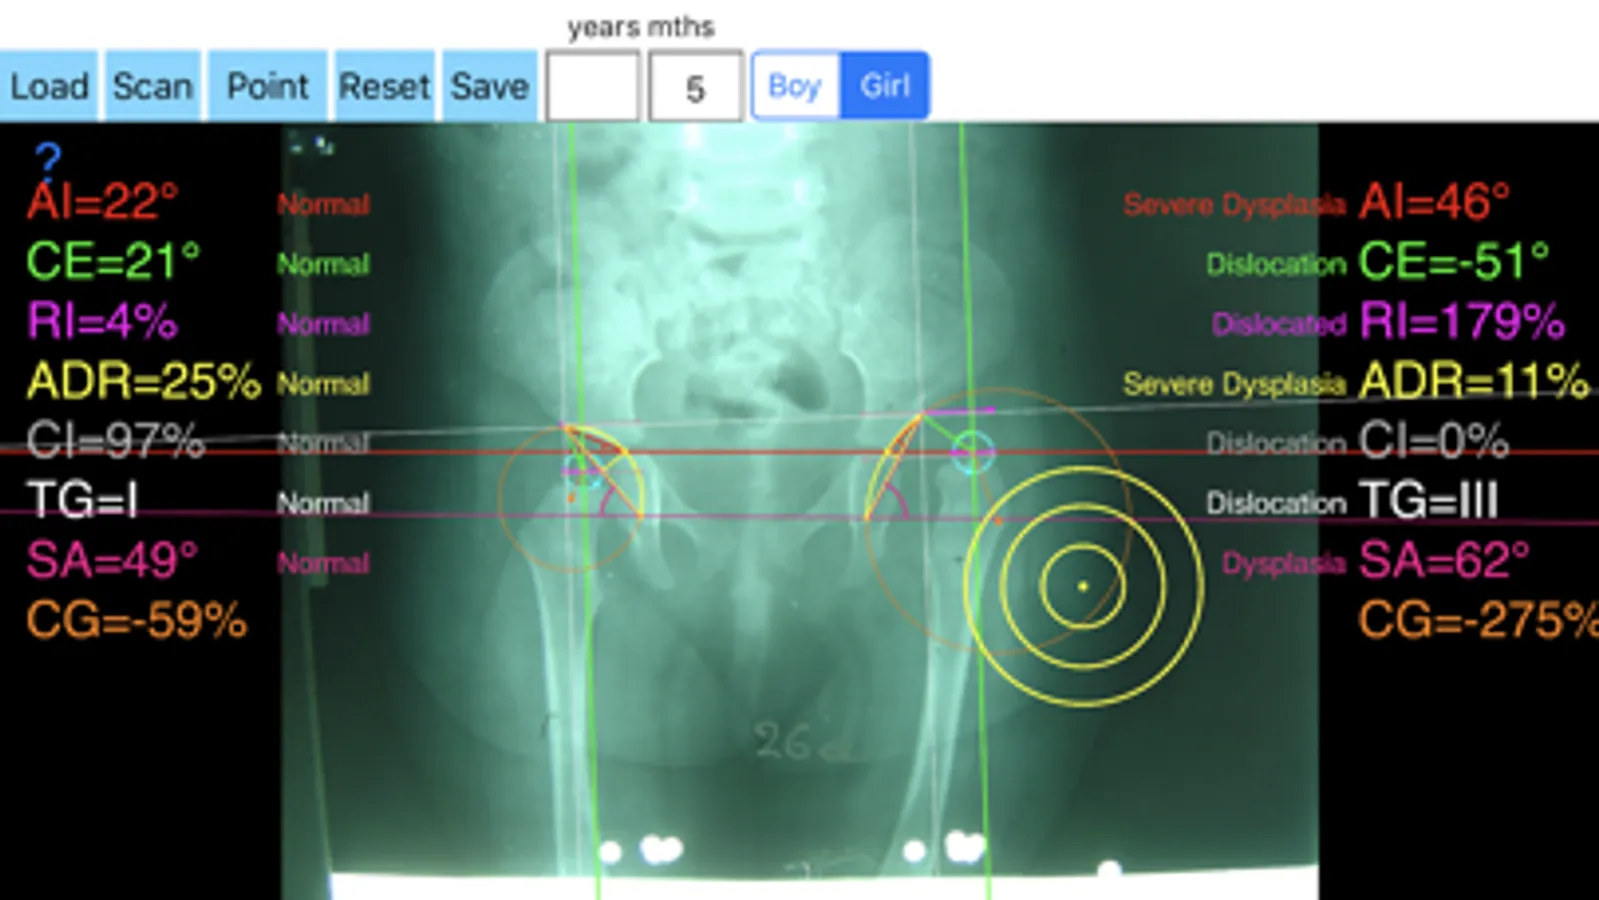

Hip dysplasia leads to premature osteoarthritis of the hip and accounts for many of total hip replacements in patients. The early diagnosis is extremely important and is based mainly on the radiological findings. In a radiographs correctly performed measurements of Indexes like the Acetabular Index (AI), the Center-Edge (CE), the Acetabular Depth-Width Ratio (ADR), the femoral head extrusion index or Reimer Index (RI), the Congruity Index (CI), the Sharp’s angle (SA), Tonnis grade of dislocation (TG), the Acetabular Index of the Weight-Bearing Zone (AIW) or Horizontal Toit externe angle (HTE), and Congruence Index (CG) are important for an the orthopaedic surgeon who wants objectively to asses and monitor optimally on standard radiographs the hips. These measurements usually performed in one X-ray by the traditional way which is time-consuming and cumbersome. We offer this new app, in which simply by marking five points at each hip you measure in an instant, all these indexes. The app also compares the results with normal age, gender and side specific reference databases retrieved from the international literature.

-Offers a very convenient way to determine the most accurate possibly way nine Indexes of hip dysplasia at once. By inserting the gender the age and marking five points at the same X-ray, at each hip, the App calculates the nine above mentioned indexes (AI, AIWB, CE, RI, ADR ,CI, SA,TG, CG) without to have to repeat each measurement separately. You measure all radiographic Indexes in one picture. Gender age and side-specific normal reference databases are used and in cases where values are out of normal ranges, the hips are categorized according the measured Index normal categorisation.

In a busy everyday practice, measuring in X-rays in clinical settings it is time consuming and cumbersome. Accessory instruments like protractors, goniometers, well sharp pencils, rulers or even transparent papers must be available. In case you have a packs system usually you don’t have the reference data. The app offers a very convenient and also accurate way to perform most common radiographic measurements for hip dysplasia, in a blink of an eye in front of your screen. The build in feature of the app, allows results to be compared and categorized according to gender, age and side-specific normal reference databases and help decide what could be considered normal or pathologic.